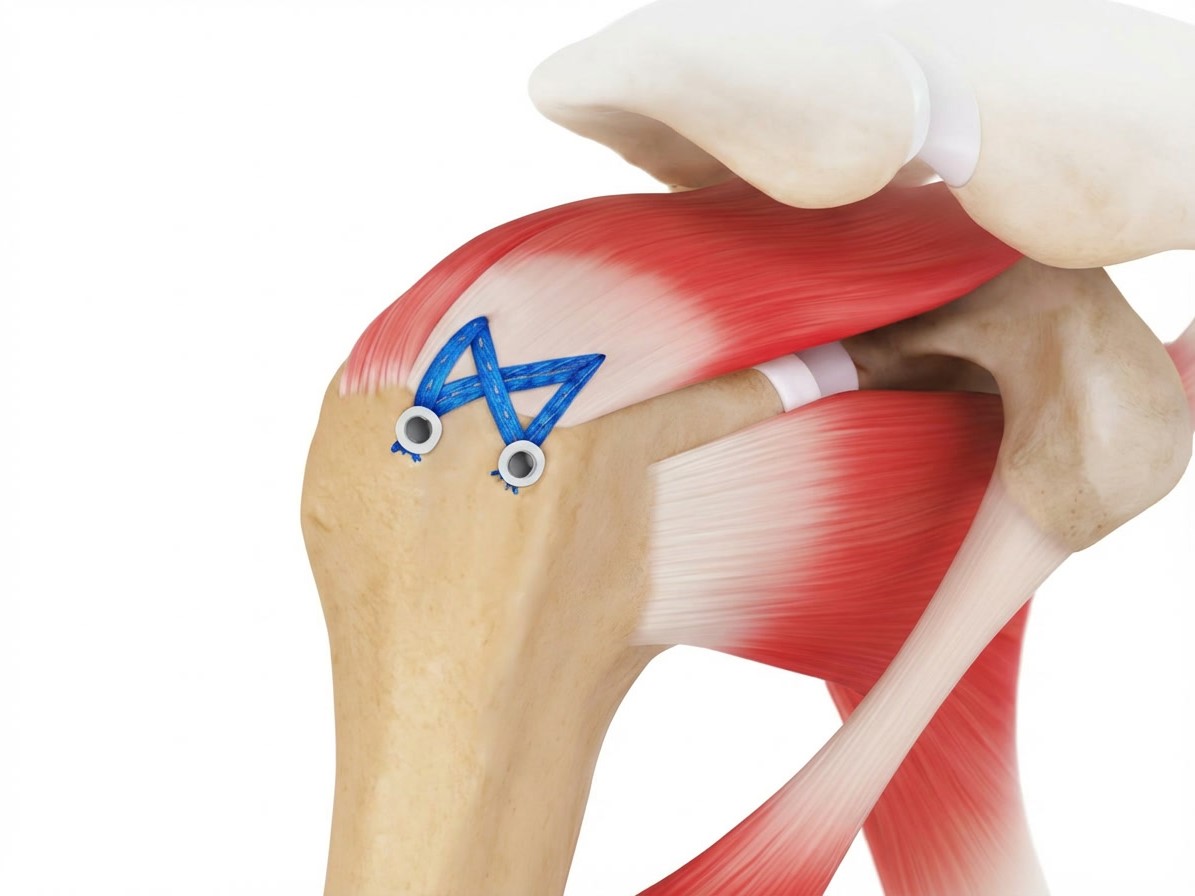

Naht und Refixation

• Verwendung von Fadenankern (Suture Anchors), die im Humeruskopf eingebracht werden. Die Sehne wird mit Fäden durchstochen und zur Knochenoberfläche zurückgeführt.

• Single-Row-Technik: Eine Reihe von Ankern entlang des Footprints.

• Double-Row-Technik: Zwei Reihen für breitere Kontaktfläche (höhere Stabilität).

• Suture-Bridge-Technik: Verbindung beider Reihen